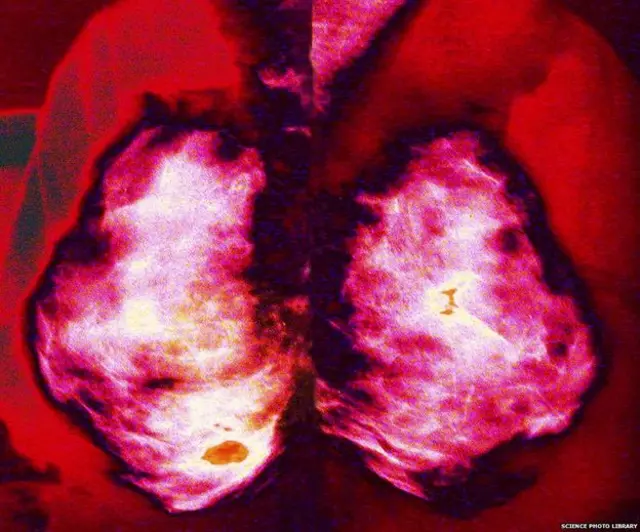

Las mujeres británicas de entre 50 y 70 años pueden realizarse una prueba para detectar cáncer de mama de forma gratuita.

Un informe independiente que analizó la efectividad de estas mamografías concluyó que salvan 1.400 vidas al año.

Fuente de la imagen, BBC World Service

Sin embargo, instituciones de prestigio como el Centro Nórdico Cochrane en Copenhague, Dinamarca, afirman lo contrario: que tienen muy poca o ninguna incidencia y que lo que redujo la mortalidad del cáncer de mama son mejores tratamientos.